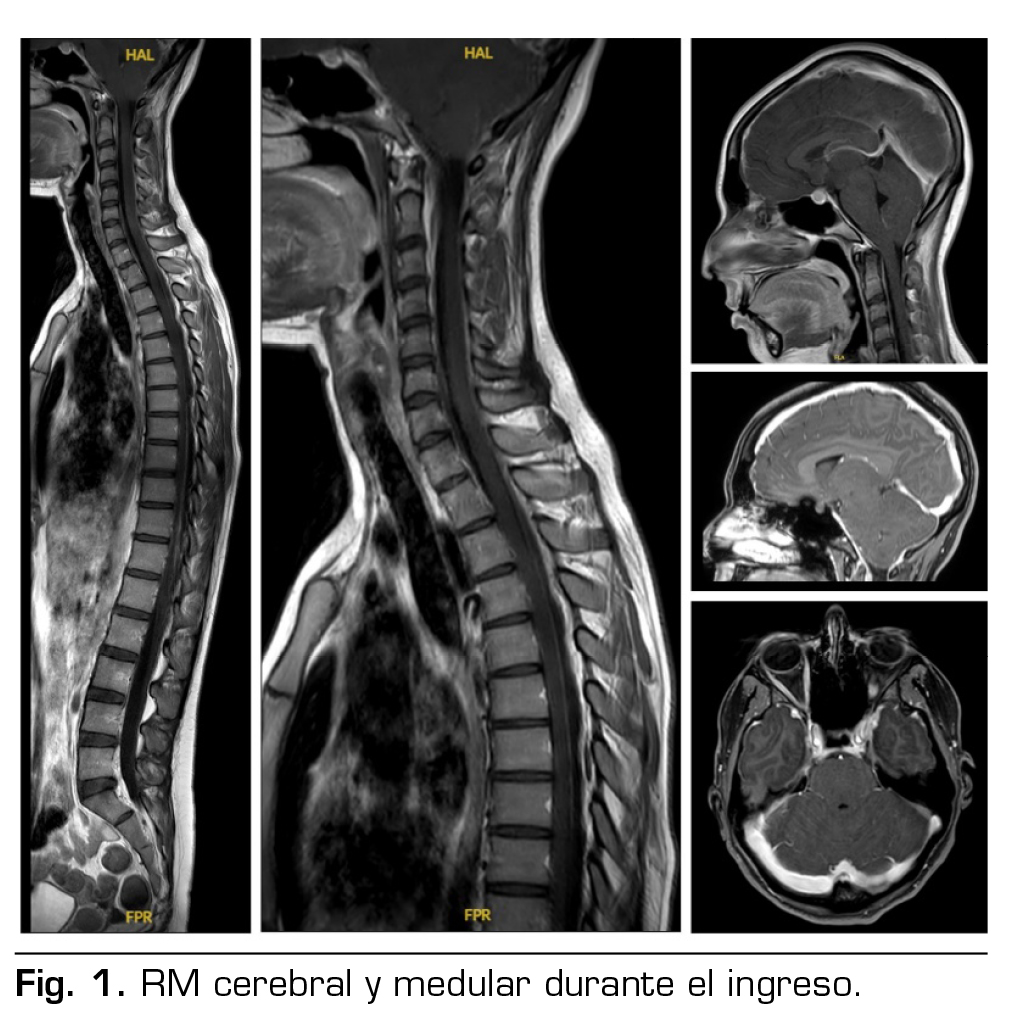

Presentación del caso: Paciente de 24 años que ingresó en Neurología por cefalea opresiva bilateral asociada a rigidez cervical y náuseas, de 25 días de evolución, valorada 2 veces previamente en Urgencias y sin mejoría con el tratamiento pautado. No se objetivó fuga de líquido cefalorraquídeo en las pruebas de imagen. Se diagnosticó de hipotensión intracraneal espontánea. Debido a la persistencia de la clínica, 13 días después del ingreso, se realizó un parche epidural hemático vía caudal, con resolución completa e inmediata de la clínica. Fue dada de alta 3 días después del parche hemático, asintomática.

Figura 1